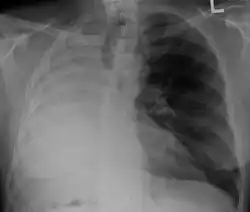

Pleural effusion

A pleural effusion is an accumulation of fluid inside the pleural space. If this collection of fluid gets large enough, it can also push structures in the chest away from it and cause a mediastinal shift. However, a pleural effusion can also pull the mediastinal structure towards itself. If this is the case, then there is an underlying condition causing the collapse of the lung on that side. An example is a tumor obstructing a bronchus and causing lung collapse and pleural effusion.[3]